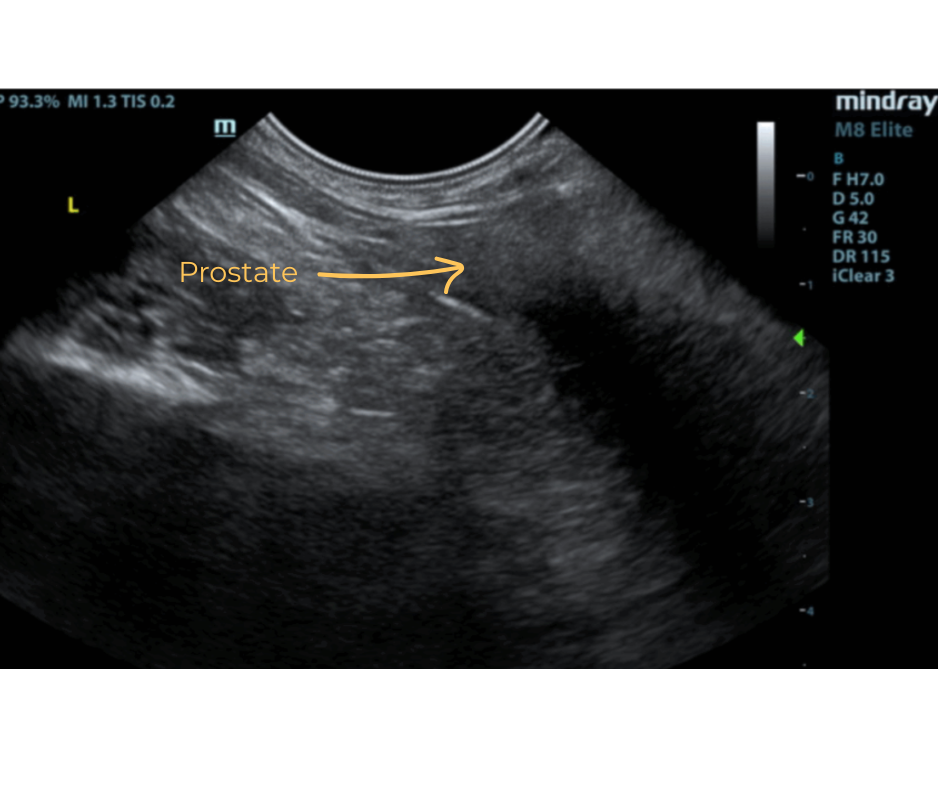

The prostate was uniform and poorly developed measuring 1.0 cm.

- Poorly developed prostate